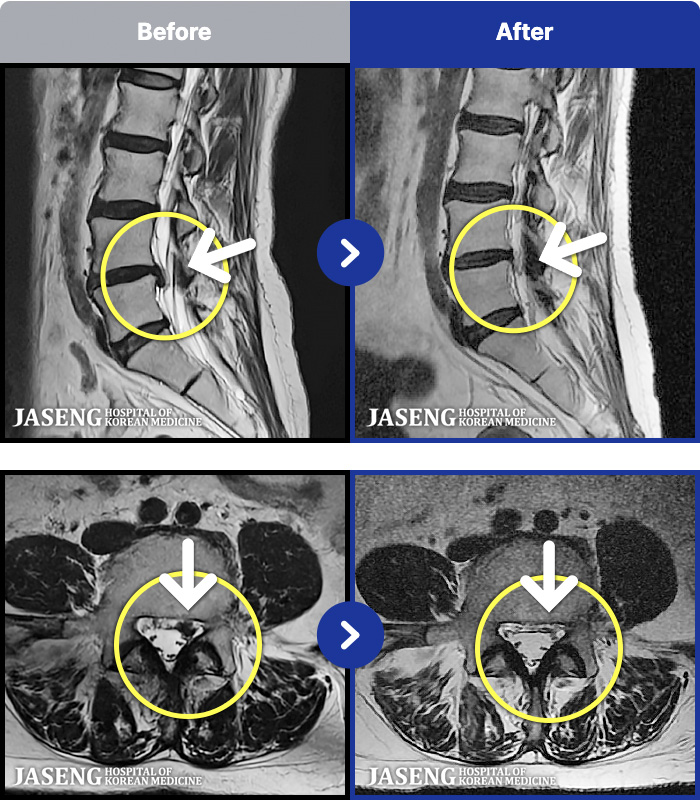

[Կñ:25.03.29~25.07.17]

[_㸮ũ] 㸮

No.52

ȸ 62

2026.01.06